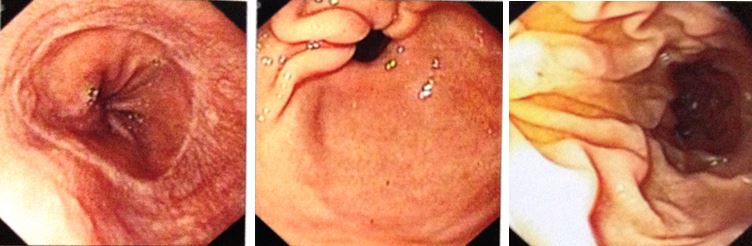

1. Nội soi phế quản: không thấy u trong lòng phế quản (hình 2)

Hình 2: Hình ảnh nội soi phế quản cho thấy không có u trong lòng phế quản

1. Nội soi đại tràng: bình thường (hình 3)

Hình 3: Hình ảnh nội soi đại tràng cho thấy đại tràng hoàn toàn bình thường